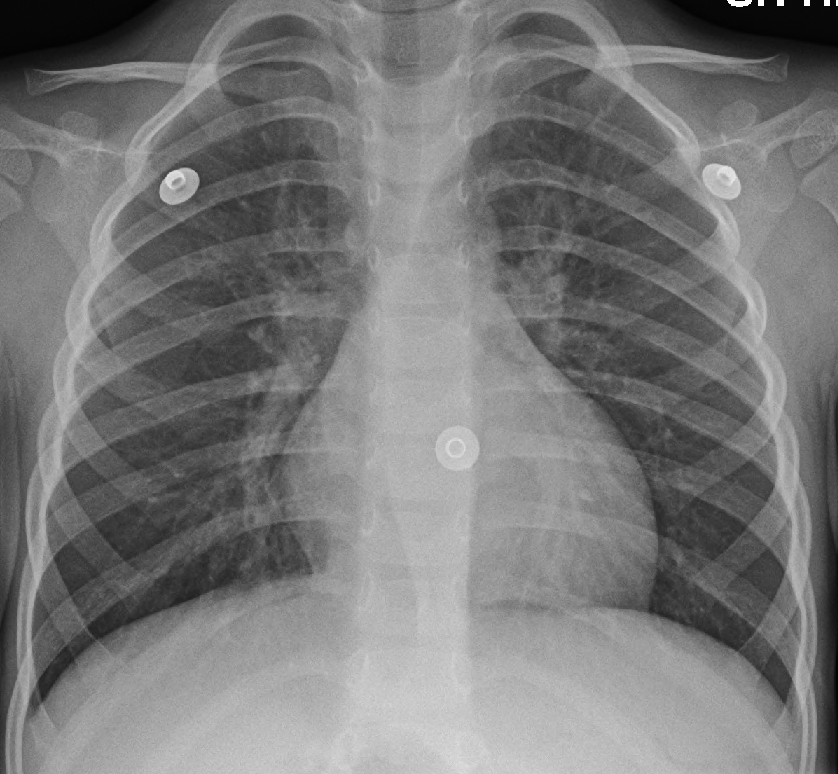

- 흉부 X선 사진: 발열, 빠른 심박수, 빠른 호흡수가 있거나 고령인 경우 더 흔한 폐렴을 배제하는 데 유용하다.[11]